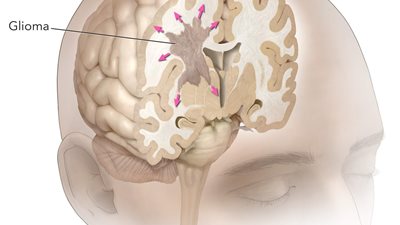

الورم الأرومي الدبقي هو سرطان سريع الانتشار ينشأ في الدماغ أو الحبل الشوكي، ويبدأ بالخلايا النجمية، وهي الخلايا التي تدعم الخلايا العصبية.

هذا السرطان العدواني، الذي يمثل أكثر من 50٪ من جميع أورام المخ الخبيثة لدى البالغين، يمكن أن يؤثر بشدة على الأنسجة السليمة وينتشر إلى مناطق أخرى من الدماغ.

تدفع هذه التغييرات الخلايا السرطانية إلى التكاثر بسرعة، وتشكيل ورم يمكن أن يضغط على الأعصاب المحيطة وأجزاء الدماغ، مما يسبب الأعراض ومزيد من المضاعفات.